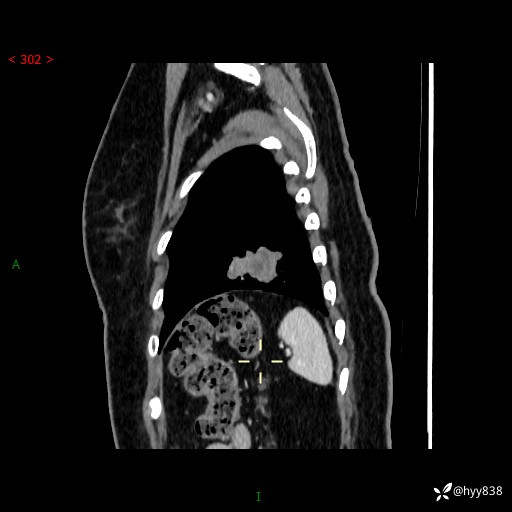

【现病史及既往史】:患者自诉2月前体检发现肺结节(左肺下叶约17mm,右肺上叶4mm),未予特殊处理,2024-10-12当地市第五医院门诊复查胸部CT提示右下肺结节(大小约3.3cm*3.9cm),患者无咳嗽、咳痰,无畏寒、发热、盗汗,无咯血,无胸闷、胸痛、呼吸困难,无恶心、呕吐,无腹痛、腹胀、腹泻等不适,现为求进一步诊治,门诊以“孤立性肺结节”收住我科。 患者本次起病来精神、食欲、睡眠尚可,大小便正常,体力、体重无明显变化。

【检查】:胸部CT增强检查